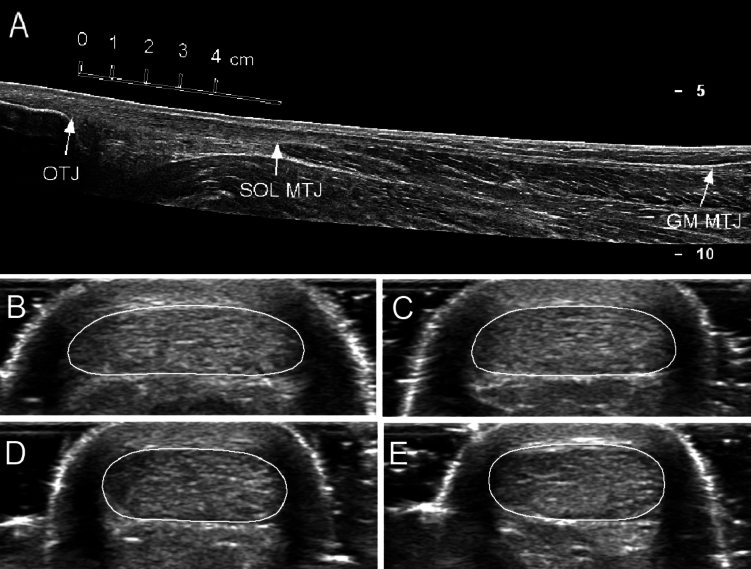

本研究的目的是调查(i)来自英语一级学院(ASP)的成年男性足球运动员与男性对照组(CON)之间腓肠肌内侧肌(GM)肌腱特性的差异;(ii) GM肌腱性能与跳跃性能之间的关系。在13 ASP处测量GM肌腱的力-伸长关系(平均±SD高度1.81±0.07 m;质量73.6±5.4 kg;年龄18.8±1.2岁),11岁(1.74±0.05岁);71.2±7.6 kg;(22.3±3.0岁),采用动力测量、超声和肌电图联合检查。参与者还进行了一系列单侧和双侧反跳(CMJ)和双侧落跳。GM肌腱性能各组间无差异,但最大肌腱伸长与单侧垂直CMJ峰值功率呈负相关(r = -0.427, P = 0.037)。腿刚度和落体跳时的峰值力与GM腱刚度(r = 0.431 ~ 0.462, P = 0.035 ~ 0.023)、最大腱力和跟腱CSA (r = 0.409 ~ 0.737, P≤0.047)相关。这些结果表明,ASP和CON的GM肌腱性能没有差异,但更硬的GM肌腱可能有助于产生更大的力,以增加单侧垂直CMJ的功率输出。此外,具有更大更硬GM肌腱的更强壮的个体在跳远时可以获得更高的力和刚度输出,这可能导致更好的投球表现,并可能代表一种保护肌腱免受损伤的保护机制。

The aims of this study were to investigate (i) differences in gastrocnemius medialis (GM) tendon properties between adult male soccer players from an English category one academy (ASP) and male control participants (CON); and (ii) the relationships between GM tendon properties and jump performance. The GM tendon force-elongation relationship was measured in 13 ASP (mean ± SD height 1.81 ± 0.07 m; mass 73.6 ± 5.4 kg; age 18.8 ± 1.2 years) and 11 CON (1.74 ± 0.05 m; 71.2 ± 7.6 kg; 22.3 ± 3.0 years) using a combination of dynamometry, ultrasonography and electromyography. Participants also performed a series of unilateral and bilateral countermovement jumps (CMJ) and bilateral drop jumps on a force platform. GM tendon properties did not differ between groups but maximal tendon elongation correlated inversely with unilateral vertical CMJ peak power (r = -0.427, P = 0.037). Furthermore, leg stiffness and peak force during a drop jump correlated with GM tendon stiffness (r = 0.431-0.462, P = 0.035-0.023), maximal tendon force and Achilles tendon CSA (r = 0.409-0.737, P ≤ 0.047). These results suggest that GM tendon properties do not differ between ASP and CON but a stiffer GM tendon may facilitate the production of larger forces to increase power output during a unilateral vertical CMJ. Furthermore, higher force and stiffness outputs are achieved during a drop jump by stronger individuals with larger and stiffer GM tendons, which could lead to greater pitch-based performance and may represent a protective mechanism to shield the tendon against injury.